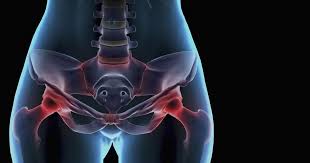

A ct scan of the pelvis should include the hip bones so one would likely pick up a bone cancer like ewing sarcoma, osteosarcoma or chondrosarcoma. Thanks for the feedback thanks for the feedback. While bone cancer does not typically cause breaks or fractures, the condition can significantly weaken the bones, which can lead cause severe, sudden pain if an adjacent healthy bone is injured. Then it can become more severe and steady later. Ewing sarcoma tumors most commonly arise in the pelvis, legs or arms of children and young adults.

Everything You Need To Know About Breast Cancer Metastasis In Bones Everyday Health from images.everydayhealth.com Other conditions, like osteoporosis or arthritis. During a bowel movement, the puborectalis is if the muscle does not relax or contracts during paradoxical contraction, it may feel like you are. What are bone cancer symptoms? Learn more about the symptoms, risk factors, diagnosis, types, treatment, and outlook for bone cancer. The most common symptom of bone cancer in the hip is hip pain, which can be severe enough to disrupt sleep and daily activities. Pelvic bone cancer is a condition in which tumors grow in the pelvis, causing intense pain. Common symptoms of cancer treatment for. While bone cancer does not typically cause breaks or fractures, the condition can significantly weaken the bones, which can lead cause severe, sudden pain if an adjacent healthy bone is injured.

Who is most likely to get bone cancer? Do we know why the bone behaves this way? Did this article help you? Do you believe your eating habits to be healthy? Where can you find the necessary information? Lung cancer with bone metastases refers to the spread of cancer from the primary (original) tumor the pain may initially feel like a dull muscle strain but gradually worsen and become severe. Less common symptoms can include A ct scan of the pelvis should include the hip bones so one would likely pick up a bone cancer like ewing sarcoma, osteosarcoma or chondrosarcoma. How many meals a day do you have? What does bone pain from cancer feel like? It will also help you understand what to expect a total pelvic exenteration is a surgery to remove organs from your urinary, gastrointestinal, and gynecologic systems. Cancers in the bones of the neck can cause a lump in the back of the throat that can lead to trouble swallowing or make it hard to. Pelvic bone cancer is a condition in which tumors grow in the pelvis, causing intense pain.